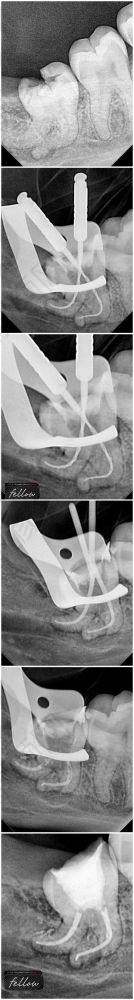

首先,医院的技术实力特别强。医生们都经过专精的培训和丰富的临床实践,对于根管治疗的各个环节都非常熟练。他们采用精良的根管治疗技术和设备,能够正确地找到根管的位置,完全清除根管内的感染物质,确保治疗的成效。